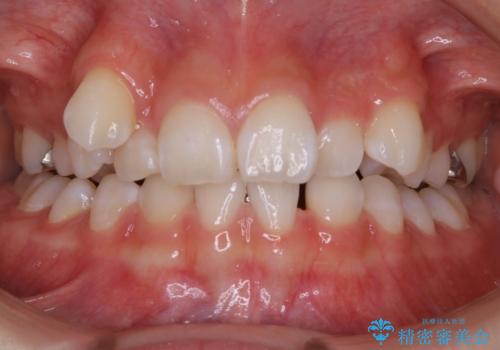

【モニター】前歯のデコボコをインビザラインで改善

担当医 藤巻太一朗

深い咬み合わせとデコボコの歯列をワイヤー矯正で改善